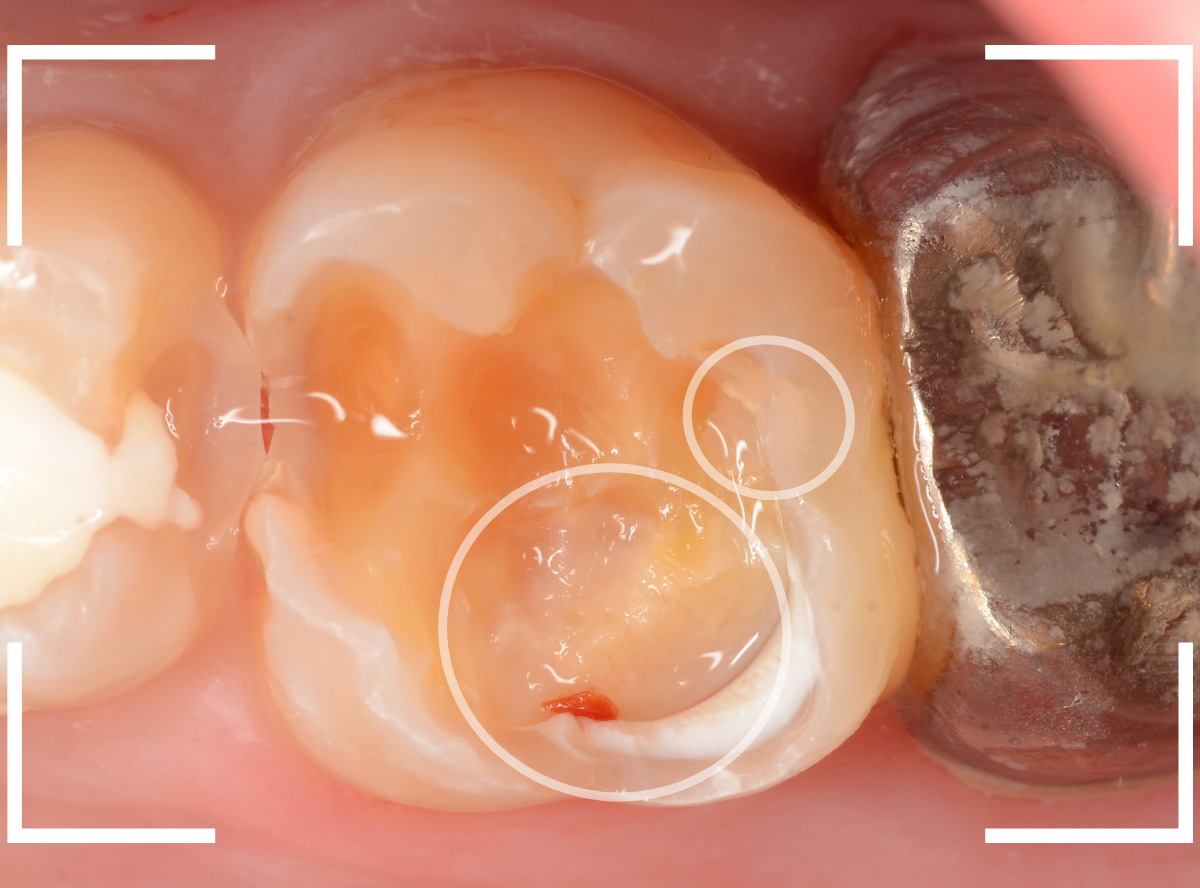

こちらが、お口の中を見たところです。

〇部の中に虫歯があると思われます。

今回のように、金属のつめ物やレジン治療をしてある歯の側面の虫歯の診断はわかりづらく、難しいです。

金属のつめ物を外したところです。

この白いセメントの中に虫歯があると思われます。

セメントを除去したところです。

赤く染まっている部分が虫歯です。

真っ赤ですね(^^;)

慎重に虫歯を除去していきましたが、まだ薄く染まっています。

もう少し除去する必要があります。

全ての虫歯が取れました、かなり深い神経まで近い虫歯でした。